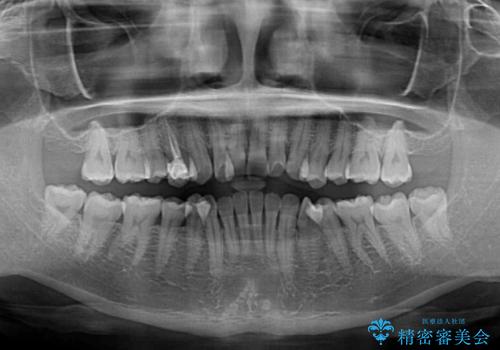

上顎歯列が下顎の歯列に対して狭小であり、一部下顎の奥歯が上顎よりも外側に位置している状態でした。

上顎の急速拡大装置を使用して上顎骨を側方に拡大することで上顎歯列を拡大し、下顎歯列も拡大できるようにすることで、歯列を整えることとしました。

歯列矯正では基本的に骨格を改善することはできませんが、急速拡大装置(MARPE)を使用することで上顎骨を側方に拡大させることができ、咬合状態を大きく改善することができます。